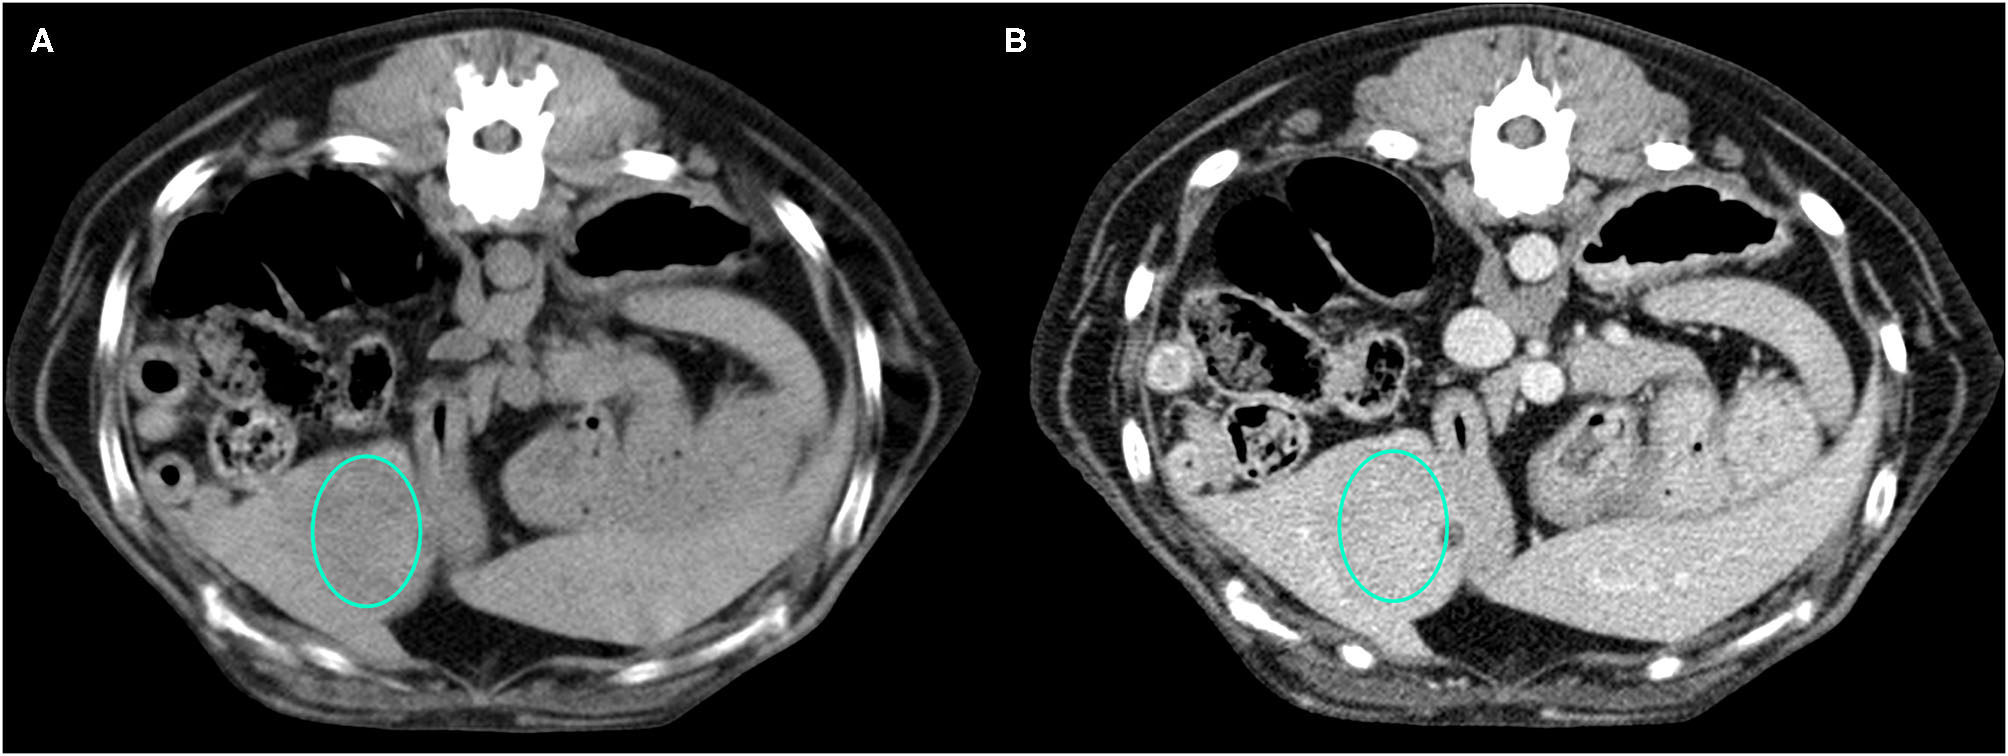

Figure 2

Example of an OBL lesion (diagnosed as adenoma) showing hyperattenuation and hypoenhancement, diffuse contrast enhancement pattern, with homogeneous distribution, well-defined margins, regular surface, and cyst-like appearance. (A) image obtained from the pre-contrast scan; (B) image obtained from the delayed scan. A ROI is placed inside the lesion in both. Based on the developed decision tree this lesion was classified as OBL.